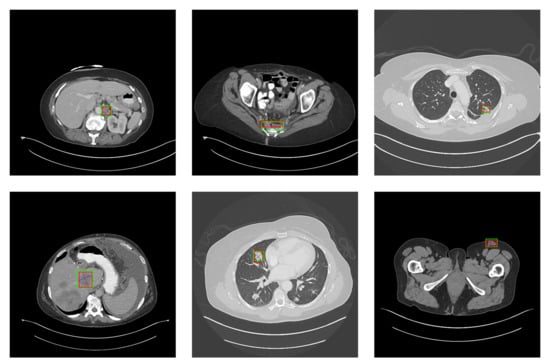

5.2. Detection Results

For further comparison, we extracted six images from the CT image series of DeepLesion. These images were taken from different sites of lesions and different areas of lesions, showing the detection results of the comparison model as comprehensively as possible. Figure 10, Figure 11, Figure 12, Figure 13, Figure 14, Figure 15, Figure 16, Figure 17, Figure 18 and Figure 19 show the detection results. All green boxes represent ground truth; red boxes denote predicted bounding boxes. It can be seen that Faster-RCNN performs very poorly on small lesions and lesions that are not easy to identify, while YOLO v3, YOLO v4, and SSD series perform relatively well. However, the aspect regression of the bounding box at small lesion locations is still not accurate. On the other hand, EfficientDet, Mask-RCNN, and YOLO v5 perform relatively well and detect lesions accurately. This may be related to the attention extraction module in these networks.

Figure 12.

The detection results of YOLO v5 in the DeepLesion dataset. The green box marks the location of the lesion.